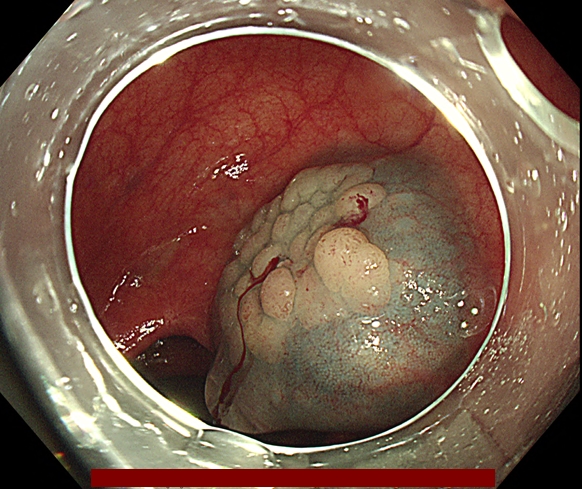

조직 검사 단독으로는 악성 세포의 존재를 배제하거나 악성 세포가 있다는 것을 확증하는데 부적절합니다. 다음 그림과 같이 악성세포가 용종에 존재하지만 조직검사로는 정상 조직을 얻을 수 있기 때문에 용종절제술로 일괄 절제해야 합니다.

오로지 용종을 완전 절제해야만 정확한 조직학적 진단이 가능합니다.

다음은 대장내시경 중 발견된 용종을 일괄 절제한 과정입니다.